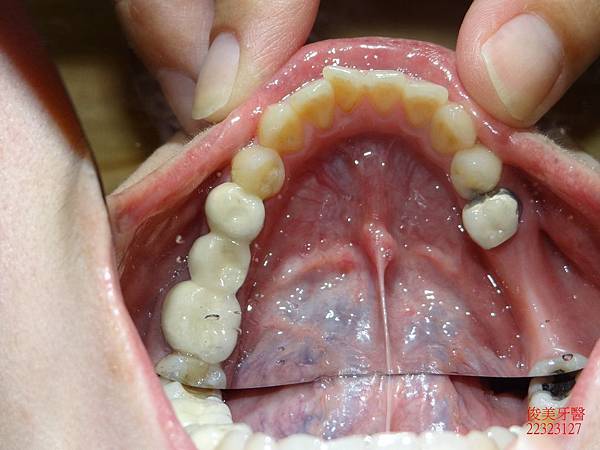

蛀牙過多,且深。牙弓形狀已非標準形態。

下顎狀況 。